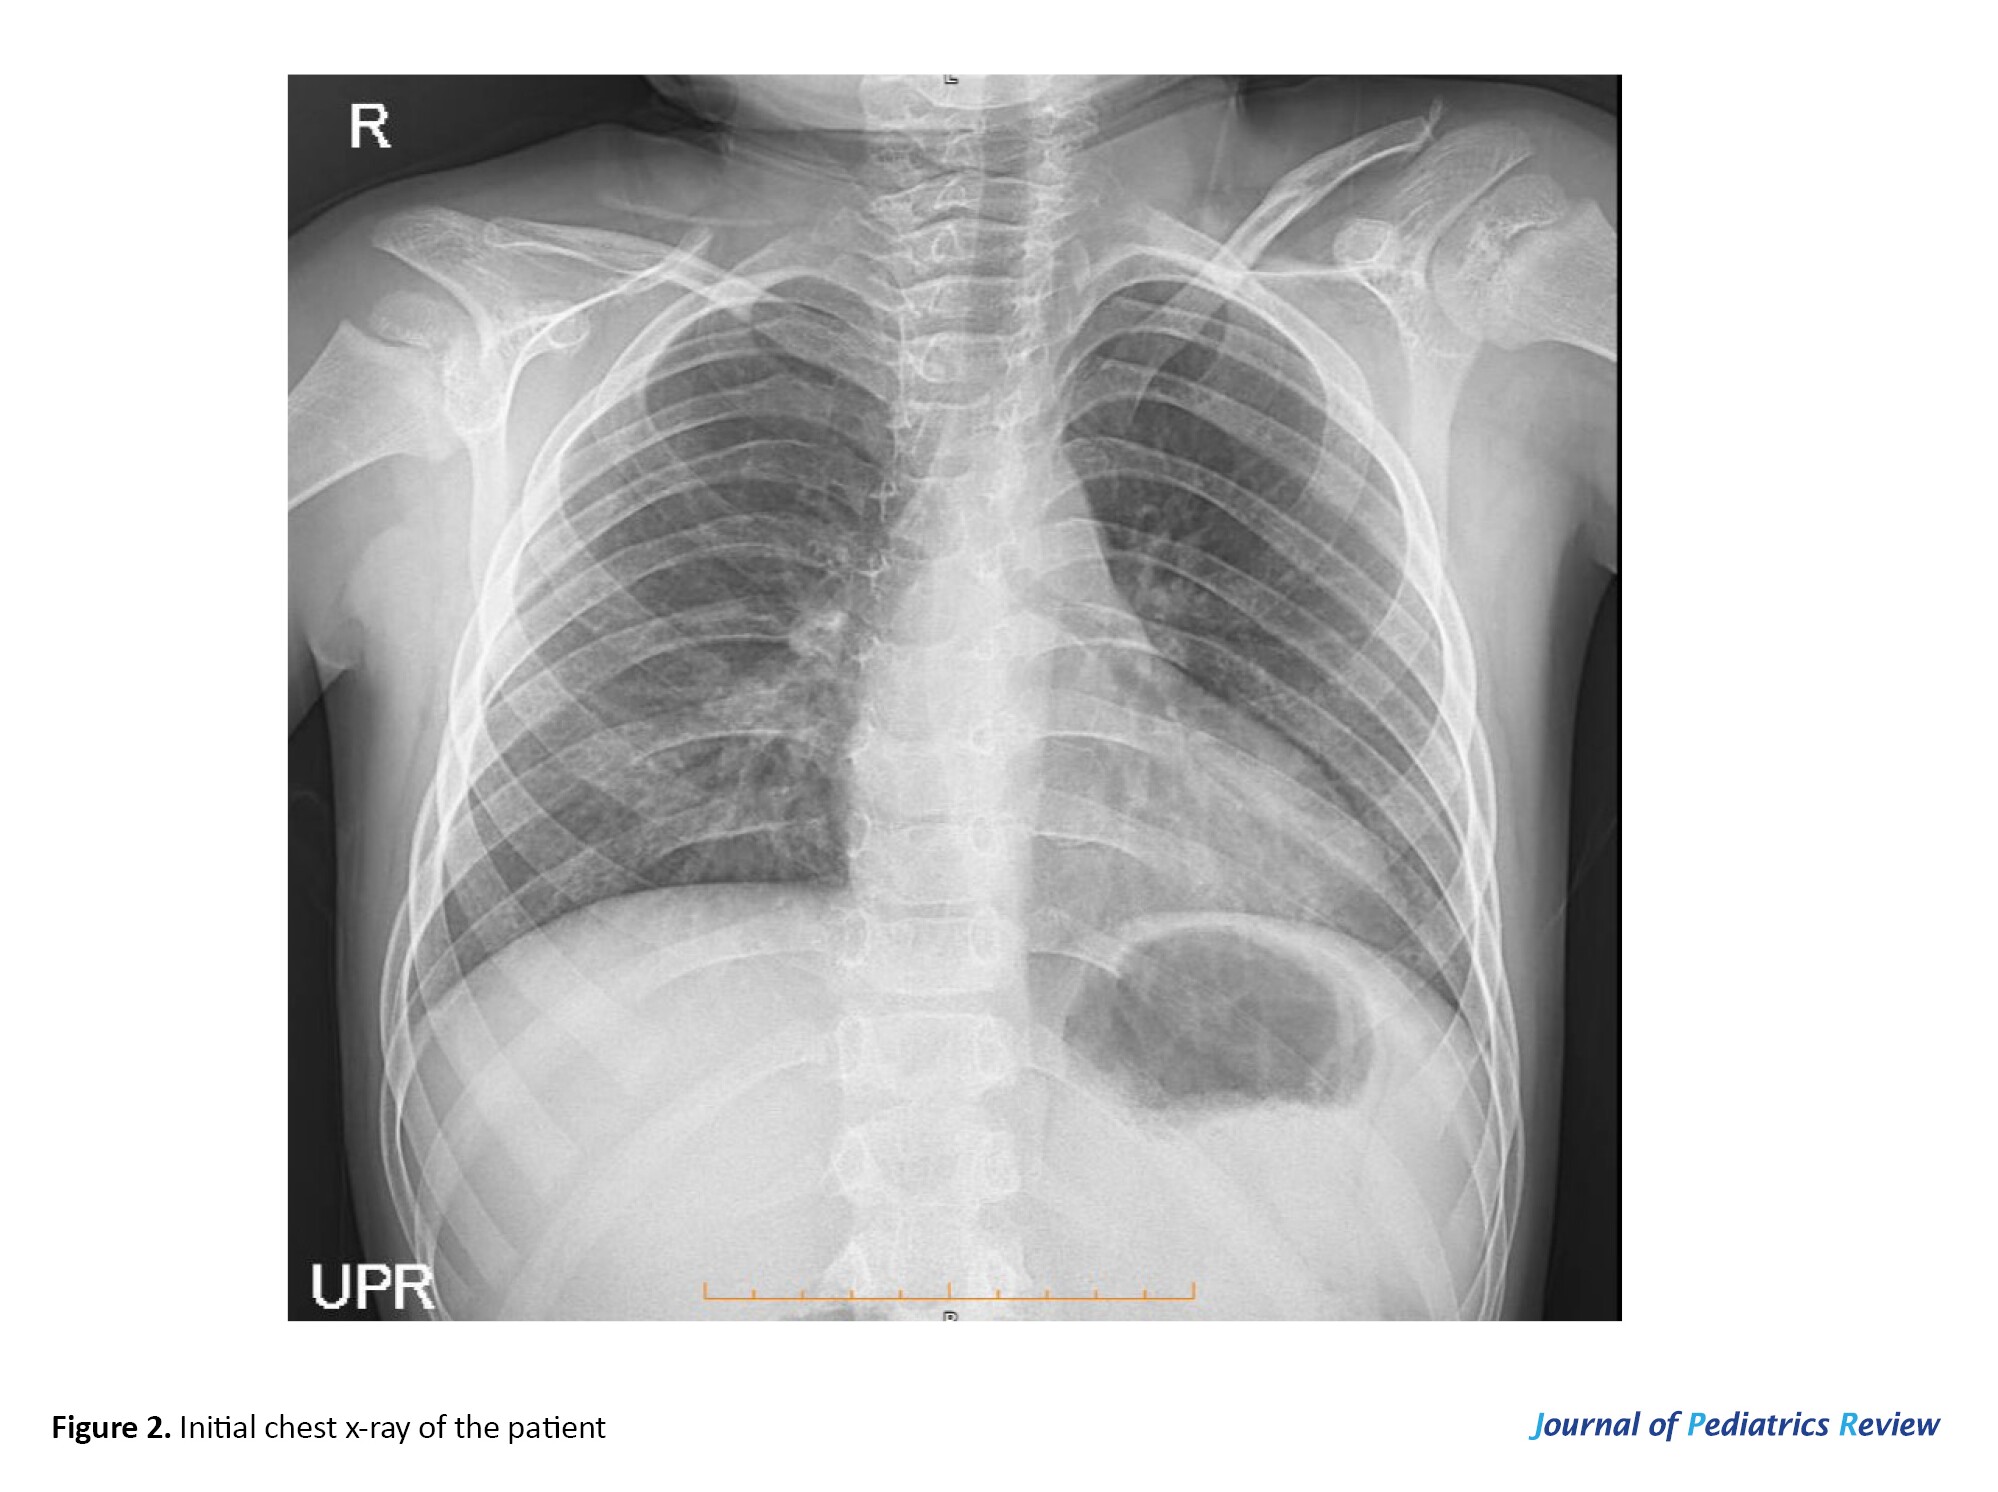

His electrocardiogram was normal, and echocardiography evaluation revealed normal left ventricular systolic function with 60% ejection fraction and normal proximal coronary arteries with no sign of vegetation or clot. However, trivial mitral regurgitation and tricuspid regurgitation were detected. Abdominopelvic sonography was normal, and due to positive P-ANCA and a history of DAH, a paranasal sinus computed tomography scan was ordered, which was intact. Figure 2 presents the initial chest x-ray.